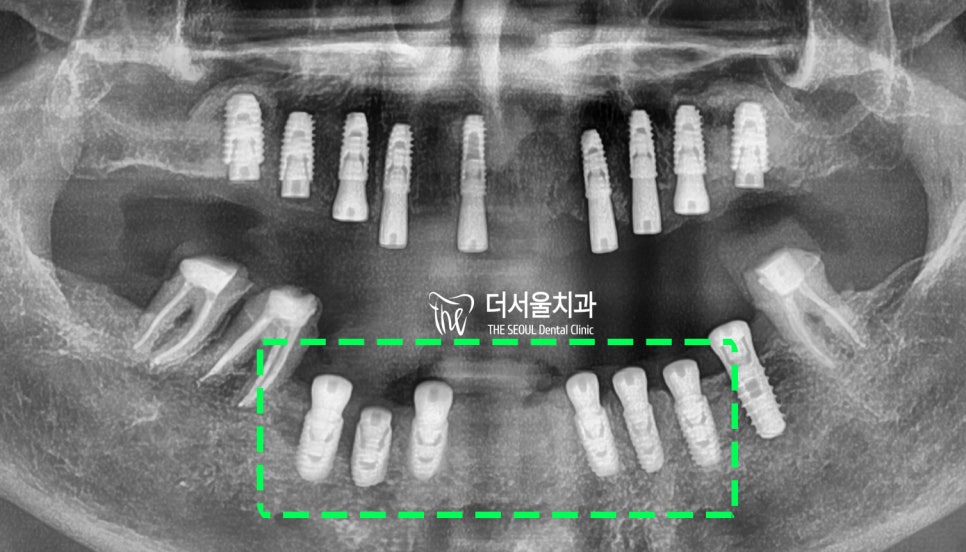

엑스레이로 확인한 결과,

치아가 왜 그렇게 흔들리는지 알 수 있었습니다.

이미 잇몸뼈가 내려 앉을대로

많이 퇴축되었음을 확인할 수 있었는데요.

뿌리 끝만 붙잡고 있는 곳도 있으니

심하게 흔들릴 수밖에 없죠.

또, 곳곳에 큰 염증을 찾아볼 수 있구요.

살릴 수 있는 치아는 정말 소수였습니다.

아래 양쪽 끝 어금니들만 살아남았죠.

36번 임플란트, 37, 46, 47번 어금니를 제외한

모든 치아를 발치했습니다.

엑스레이 그리고 CT를 통해

한번 더 꼼꼼히 확인을 해서

잘 들어갔는지 봅니다.

계획했던 대로 잘 들어갔네요. ^^

식립하고 엑스레이와 CT를 찍어봤는데,

좋은 결과가 나왔네요. ^^

엑스레이로 최종 확인까지 거쳐서

전반적으로 임플란트 수술이

잘 이뤄진 것을 확인했습니다.